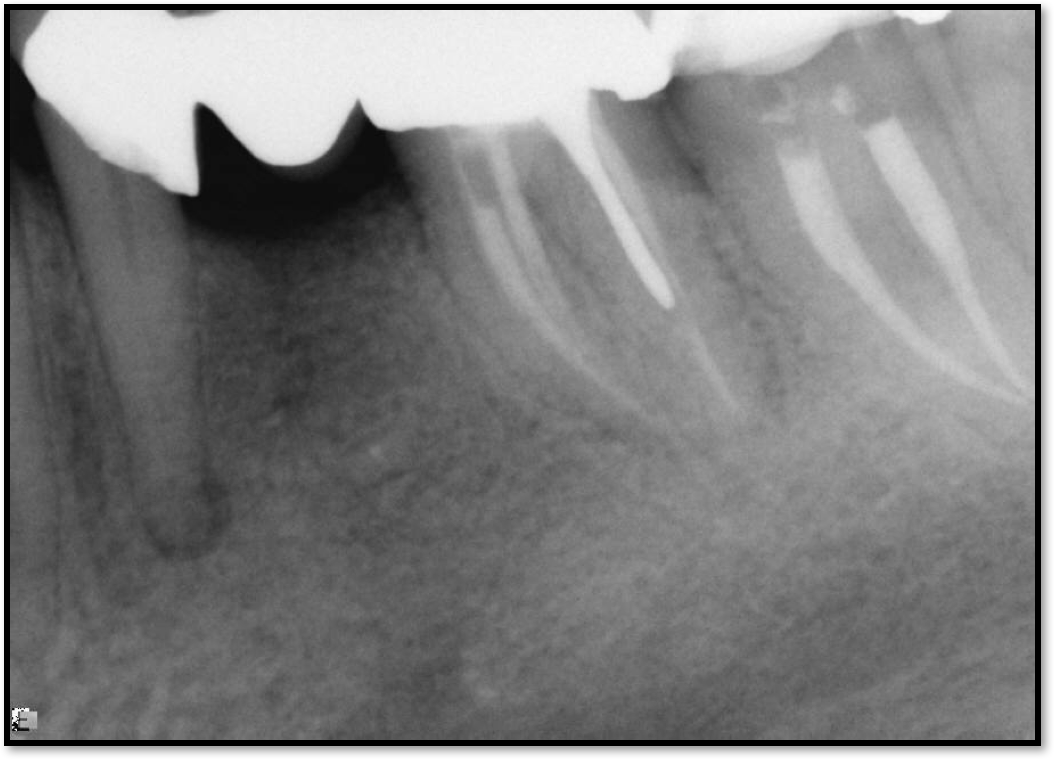

The rules for placement of a post depend on good retention: the greater the length, the greater the retention.3 Also, two-thirds of the length of the root is ideal, but 4 to 5 mm of apical gutta-percha is essential because anything less than that will disrupt the seal.8 Figure 14 shows a case where a patient had a post, core, and crown. The threaded post was shorter than ideal because the tooth was longer. Not visible was the mental foramen underneath. The patient did not have the financial resources to have the case redone. However, when the post would be removed, the clinician would need to trephine or use an ultrasonic around it, making the access bigger than an ideal conservative access. Potentially, the crown would come off. The patient did not have finances for re-treating the tooth and could not have an apicoectomy because the mental foramen was directly under the tooth.

The options, therefore, were to extract it and put a bridge or an implant in later when funds were acquired, or, as was done in this case, perform an intentional replant. The clinician extracted the tooth, cut it, placed MTA, and then put it back under occlusion using sutures—although the clinician would normally put composite in each corner to maintain it and would not etch. Usually after 2 weeks, there is stability. Figure 15 shows the postoperative radiograph, and Figure 16 shows a radiograph 4.5 years later. The patient's probing went from 3 to 4 mm, but overall it was a success because something is always lost coronally, whether the case is a replant or an implant.

Fig 15. Postoperative radiograph.

Figure 15

Fig 16. Radiograph after 4.5 years.

Figure 16